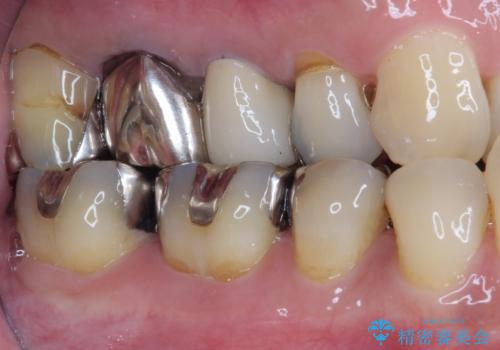

もげてしまった奥歯 オールセラミッククラウンでの補綴治療

- 食事中に歯がもげてしまったとのことで来院された患者様です。

レントゲン写真から、特に大きなむし歯などは認められませんでしたが、根管治療があまり十分に行われているとは言えない状態でした。

まずは仮歯を装着し、根管治療を行った上で土台を植立し、オールセラミッククラウンにて補綴治療を行うこととしました。

反対咬合で奥歯に負担のかかる咬み合わせのため、就寝時に強い力がかからないよう、マウスピースを装着していただくよう指示をしました。